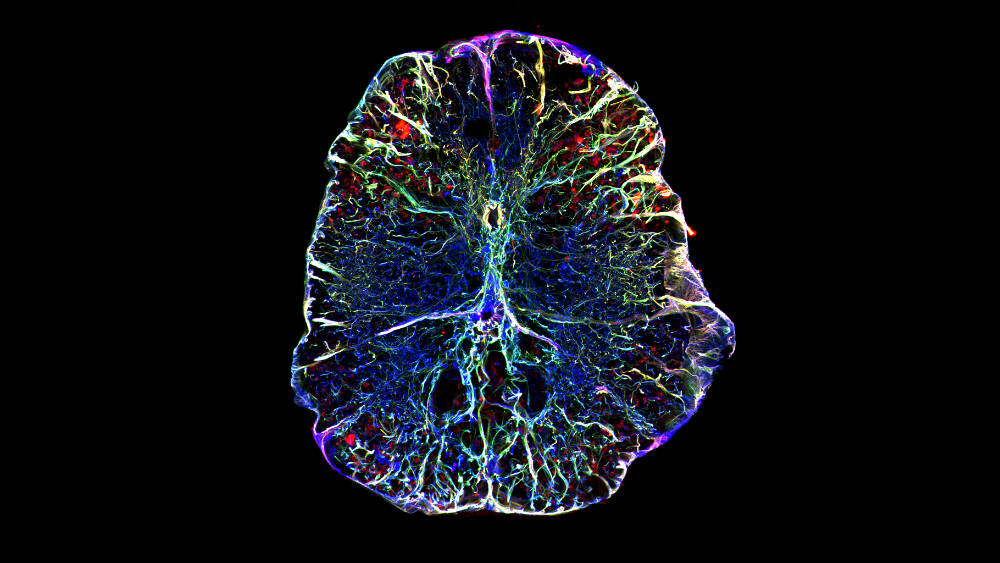

Cross section of the zebrafish spinal cord (microscopy image)

Cross section of the zebrafish spinal cord. Radial glia is labelled by IHC. © Dr. Volker Kroehne (Reimer Lab)